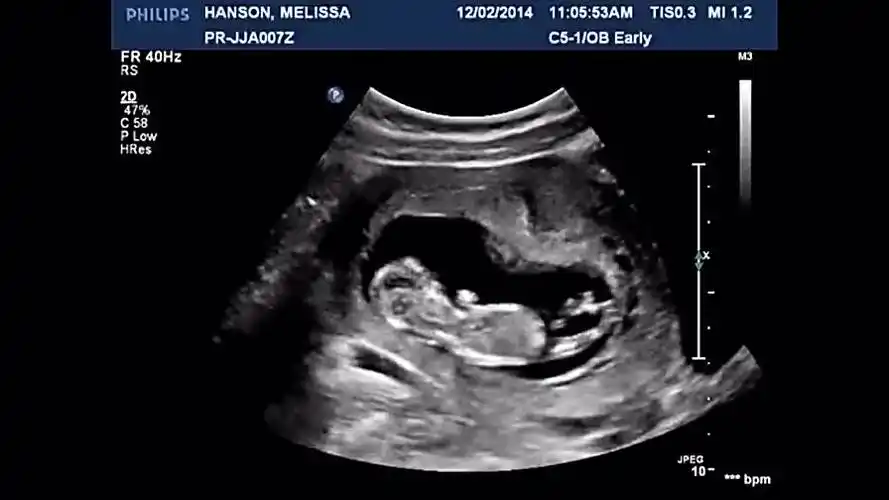

恭喜!杨佑宁晒未婚妻照和b超照 官宣当爸爸

b超影像记录宝宝在肚子里的所作所为-母婴亲子视频-搜狐视频

秦昊晒b超图像证实伊能静怀孕表白爱妻你辛苦了